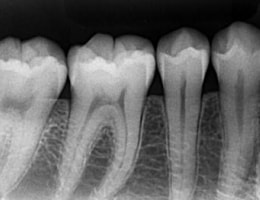

被曝量の少ない「デジタルレントゲン」を完備!

超高感度だから被曝量が軽減!子供さんにも優しいレントゲン!

デジタルレントゲンに使われているX線センサーは、デジタルならではの高感度!

照射時間が短縮され、より低線量でのレントゲン画像取得が可能となります。

また、各ユニットのデジタルモニターにも直接映像を映し出すことが出来るため、

当院のデジタルレントゲンは、

従来のフィルムを使用したレントゲン撮影に比べ、

人体に受ける放射線の量を、約1/4~1/10に抑える事が可能です。

照射時間がかなり短く、安心安全です。

大きなパノラマレントゲンは歯並びなど、全体像をつかむことにも有効的ですが、

現状を詳細に把握するため、小さいレントゲンを10枚撮って診断・治療をしております。

これにより歯石、歯周ポケット等も詳細に把握でき、緻密な治療を提供することが出来ます。